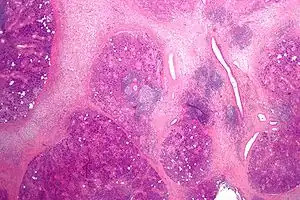

| Micrograph showing chronic sialadenitis. H&E stain. | |

Histologically, chronic sialadenitis can appear from unremarkable to a firm tan with expansion or atrophy of the lobular structure depending on the degree of inflammation and chronicity. Salivary stones (Sialolith) may be evident with cystic dilation of the salivary ducts and periductal fibrosis. Mucus extravasation may also be observed.

Common observations of chronic sialadenitis include chronic inflammatory infiltrate (lymphocytes, plasma cells and macrophages), fibrosis, acinar atrophy, mucous cell metaplasia of the ductal system is observed.